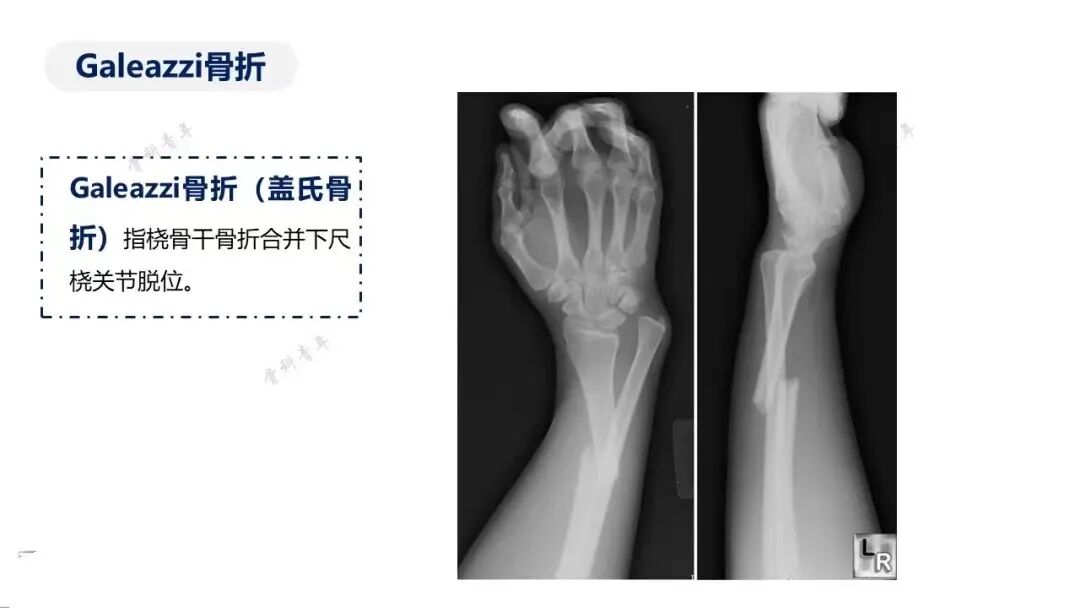

由于特殊类型骨折不属于很常见的骨折,诊断、治疗不及时往往会带来诸多更为严重的不良后遗症。今天给大家分享这40种骨折,你在临床都遇见过吗?